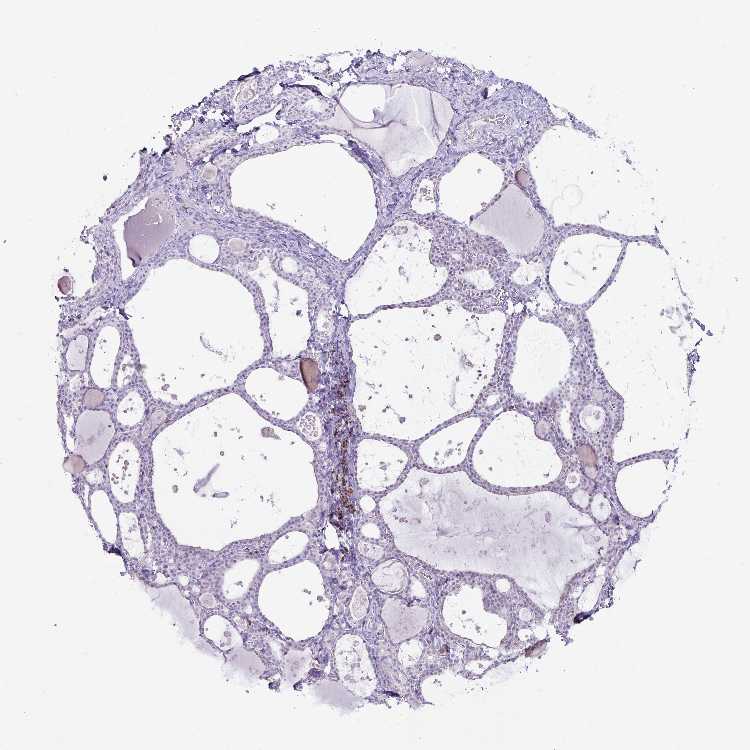

TISSUE PRIMARY DATA THYROID GLAND Show tissue menu

THYROID GLAND - Antibody stainingi

Antibody staining in the annotated cell types in the current human tissue is reported as not detected, low, medium, or high, based on conventional immunohistochemistry profiling in selected tissues. This score is based on the combination of the staining intensity and fraction of stained cells.

Each image is clickable and will lead to virtual microscopy that enables deeper exploration of all samples and also displays staining intensity scores, fraction scores and subcellular localization as well as patient and tissue information for each sample.

Antibody HPA063181Antibody HPA065895

Glandular cells Not detectedNot detected